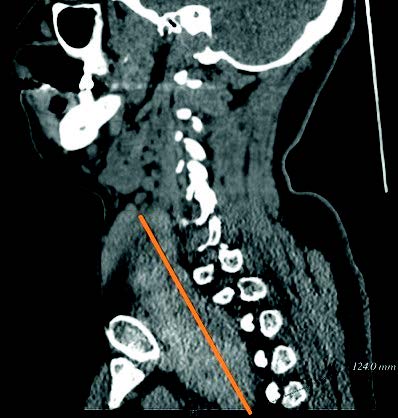

El tipo de intervención realizado ha sido en un 52,5% (N=21) de los casos la tiroidectomía total, en el 25% (N=10) de los casos se realizó una hemitiroidectomía izquierda, el 20% (N=8) hemitiroidectomía derecha y por último, en un 2,5% (N=1) se realizó una resección de un nódulo tiroideo de 4 cm completamente ectópico a la glándula tiroides, con sospecha de posible carcinoma papilar de tiroides, que tras una anatomía patológica intraoperatoria que descarta malignidad, se desestima finalmente la extirpación de la glándula tiroidea.

FIGURA 1